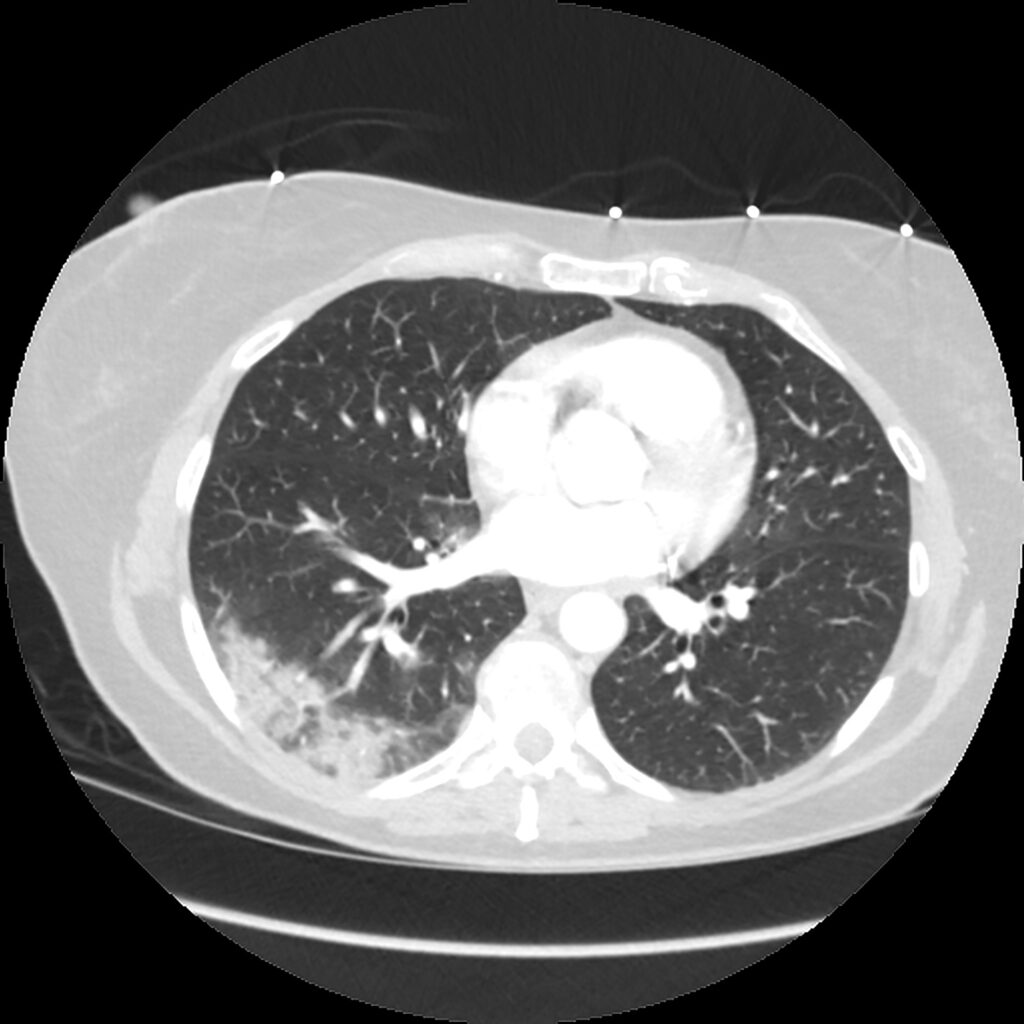

Early on, CT may be positive when the CXR is negative. The typical GGO distribution is similar, but usually more extensive than on CXR (Fig. 3).

Adenopathy, cavitation, and effusion are uncommon early on. Compared to other viral pneumonias, peripheral lower-lobe GGOs are more common in COVID-19, whereas other pneumonias tend to have more diffuse disease. There is considerable overlap, however.